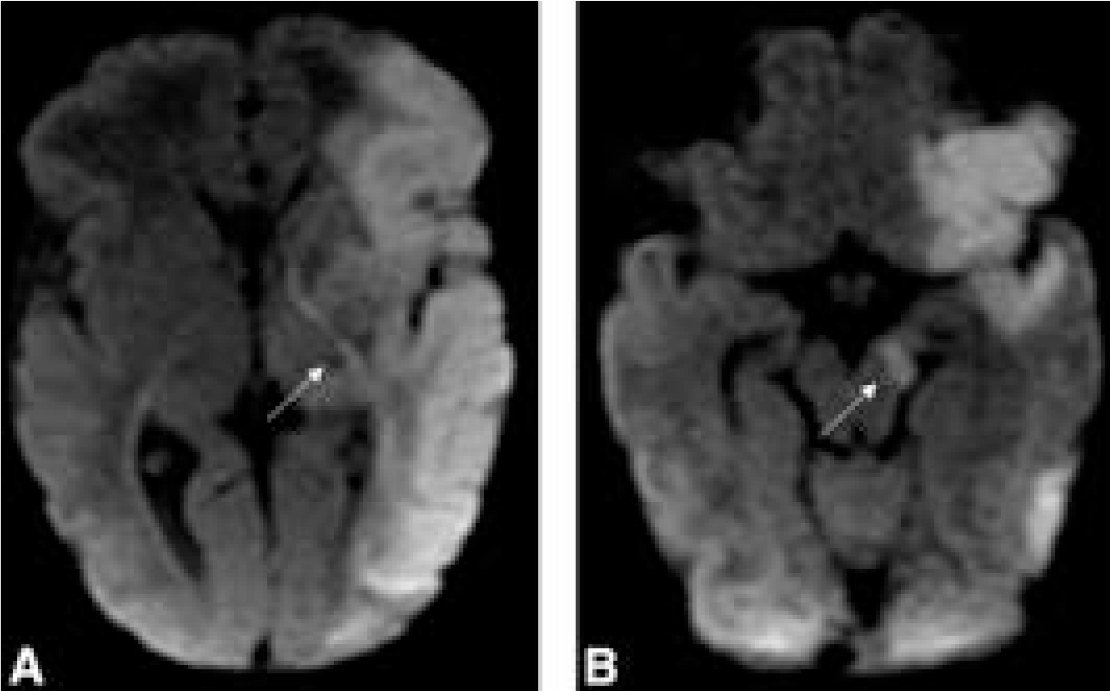

From the July-September 2025 Issue of #Neurographics: Recurrent Stroke-Like Episodes in X-Linked Charcot-Marie-Tooth Type 1 Disease: Characteristic Brain MRI Findings ow.ly/W9vt50WITmU